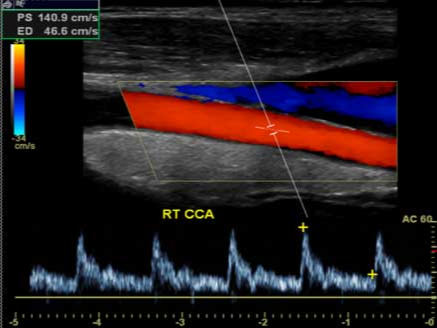

경동맥 협착증은 혈관 내벽에 콜레스테롤, 지방, 칼슘이 쌓여 혈관이 좁아지는 질환입니다. 경동맥 내경이 50% 이상 좁아지면 뇌혈류가 감소하여 뇌졸중 위험이 급격히 증가합니다. 초음파를 통해 협착 부위의 정도, 혈류 속도, 플라크의 성질(단단한지, 불안정한지)을 정밀하게 평가할 수 있습니다.

경동맥 초음파 검사는 준비 과정이 간단합니다. 공복 상태일 필요가 없으며, 목 주변의 금속 액세서리나 목도리만 제거하면 됩니다. 검사 시간은 약 10~20분 정도이며, 환자는 눕거나 고개를 약간 돌린 상태로 검사를 진행합니다. 탐촉자를 목 부위에 대고 초음파를 투사하면 화면에 경동맥의 단면이 실시간으로 나타나며, 의사는 혈류 속도와 벽의 상태를 분석합니다. 혈관이 막혀 있거나 좁아진 부분에서는 혈류 속도가 비정상적으로 증가하므로, 이를 통해 협착의 정도를 정량화할 수 있습니다.